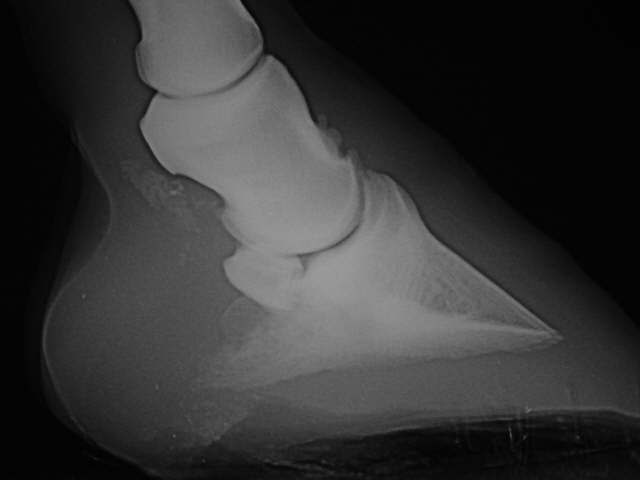

Flacher Huf

Absinken des Hufbeins im Trachtenbereich wegen Zerstörung der Verankerung des Hufbeines in der Hornkapsel und Schädigung der tiefen Beugesehne sowie Arthrose, ....